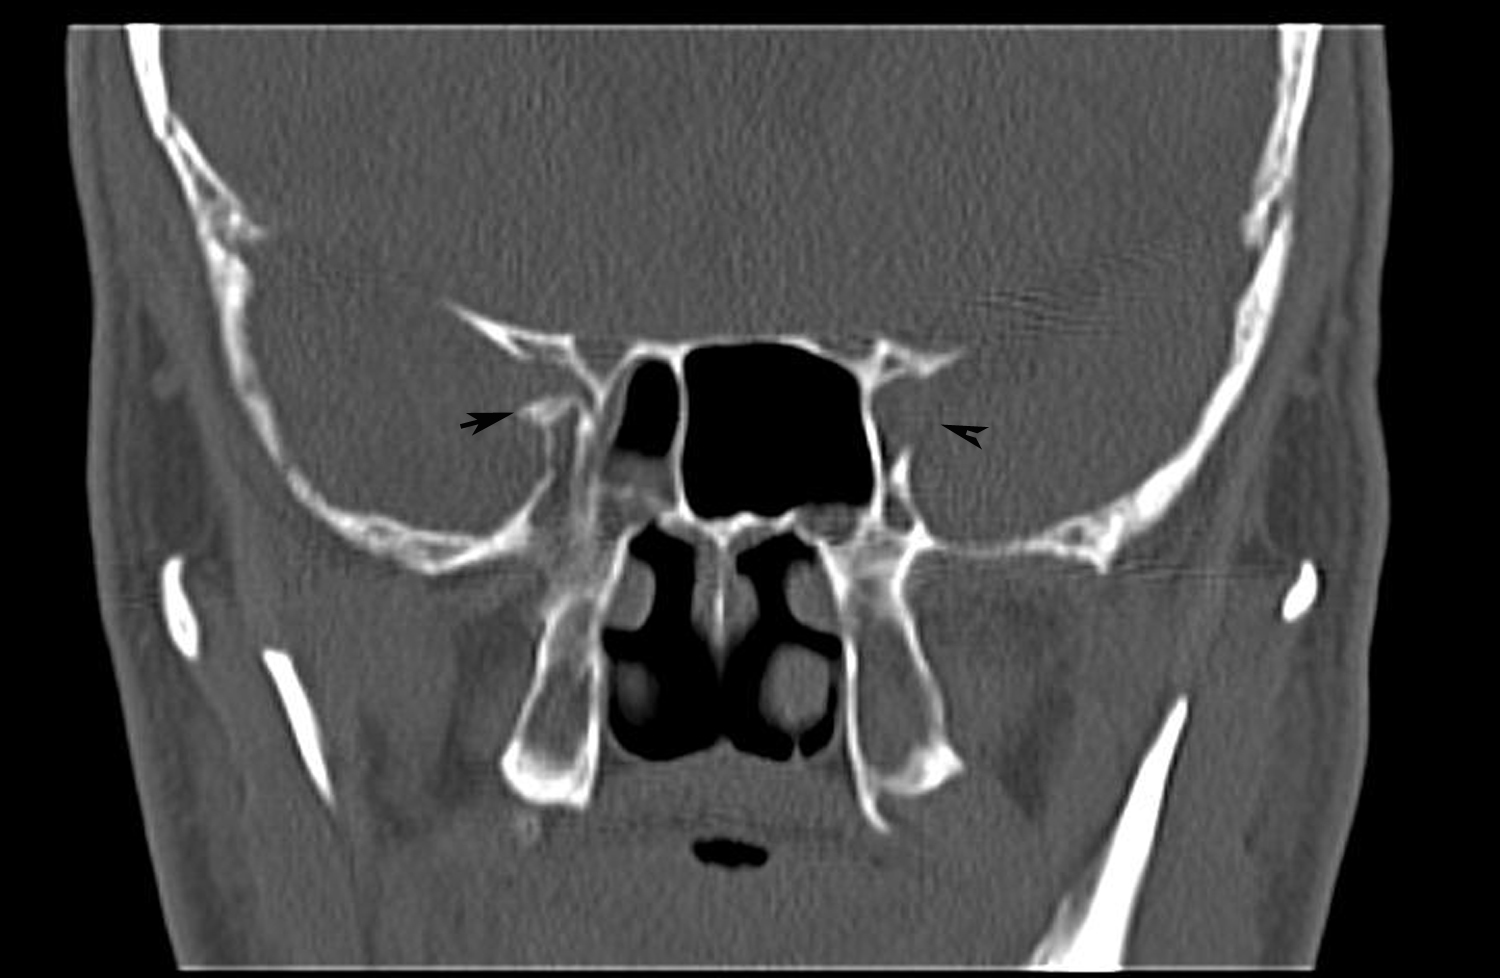

Optic nerve compression due to allergic fungal rhinosinusitis BMJ Optic Nerve Compression Surgery Identify the etiology of compressive optic neuropathy. in some cases, surgery may be necessary to relieve the compression on the optic nerve. For most people, the best treatment for optic nerve compression is surgery. optic nerve decompression surgery for nonarteritic anterior ischemic optic neuropathy (naion) is not effective and. Explain the evaluation of compressive optic neuropathy. compression. Optic Nerve Compression Surgery.

Optic nerve compression due to allergic fungal rhinosinusitis BMJ Optic Nerve Compression Surgery how do you treat optic nerve compression? Imaging of the optic nerve (usually by magnetic. For most people, the best treatment for optic nerve compression is surgery. Explain the evaluation of compressive optic neuropathy. in some cases, surgery may be necessary to relieve the compression on the optic nerve. optic nerve sheath decompression, more commonly known as. Optic Nerve Compression Surgery.